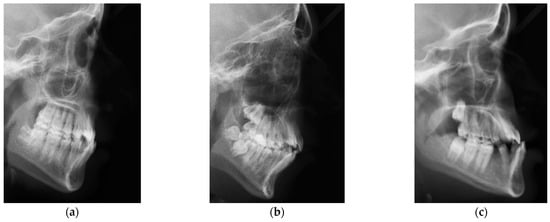

2.1. ISBI Dataset

2.2. Dicle Dataset